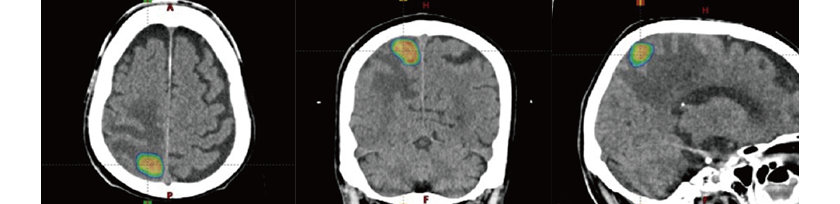

定位照射

主に脳や肺・肝臓の「小さい病変」を対象に、いろんな方向から非常に高い線量をピンポイントで患部に当てる方法。1~数回の照射で高い効果を出すことができ、患部を「焼き切る」イメージで外科手術の代わりに使われることの多い手法です。肺がん患者さんの場合、手術より高いQOL(生活の質)を維持できるというアンケート結果も。

1回当たりの線量が多いため、照射中にじっとしていなくてはいけない時間が長く、患者さんの体形などに合わせたオーダーメイドの固定具でサポートします。保険上の制約はありますが、転移があっても照射でき、近年少しずつ適用範囲が広くなってきています。